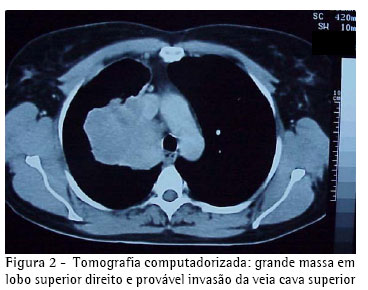

A tomografia computadorizada de tórax mostrava uma atelectasia do lobo superior direito por broncoestenose oclusiva do brônquio lobar superior, que se estendia até a porção justacarinal do brônquio principal, acompanhada de infiltração, inclusive da parede do brônquio principal esquerdo, e determinava invasão do ramo direito da artéria pulmonar e do cajado da veia ázigos. Não havia sinal de invasão da parede torácica, nem de derrame pleural (Figura 2).